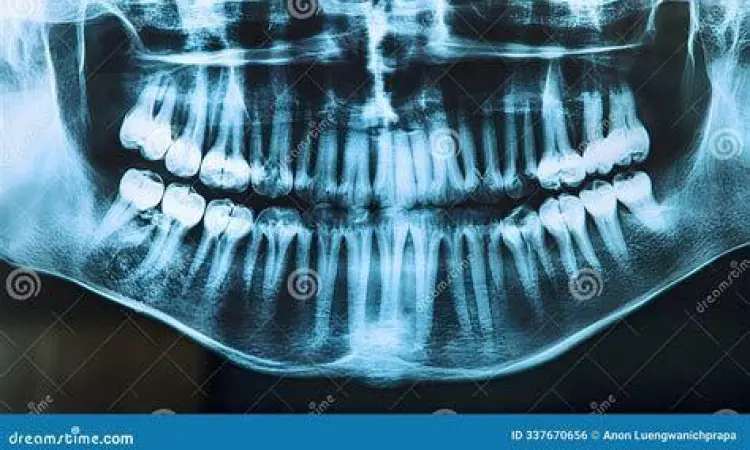

"Pencegahan jauh lebih baik daripada mengobati. Deteksi dini posisi gigi bungsu melalui rontgen panoramik sejak usia 16 tahun dapat menghindarkan pasien dari komplikasi bedah yang lebih rumit di masa depan."

Rekomendasi terbaik adalah melakukan pemeriksaan radiologi panoramik bahkan sebelum gejala muncul. Dengan melihat arah pertumbuhan sejak dini, dokter dapat memprediksi apakah gigi tersebut akan tumbuh normal atau menimbulkan masalah di kemudian hari. Keputusan untuk melakukan tindakan preventif sering kali memberikan hasil jangka panjang yang lebih baik bagi kesehatan fungsional dan estetika rongga mulut Anda. Ingatlah bahwa menjaga kesehatan gigi bungsu adalah investasi untuk kualitas hidup dan kenyamanan makan Anda di masa tua nanti.